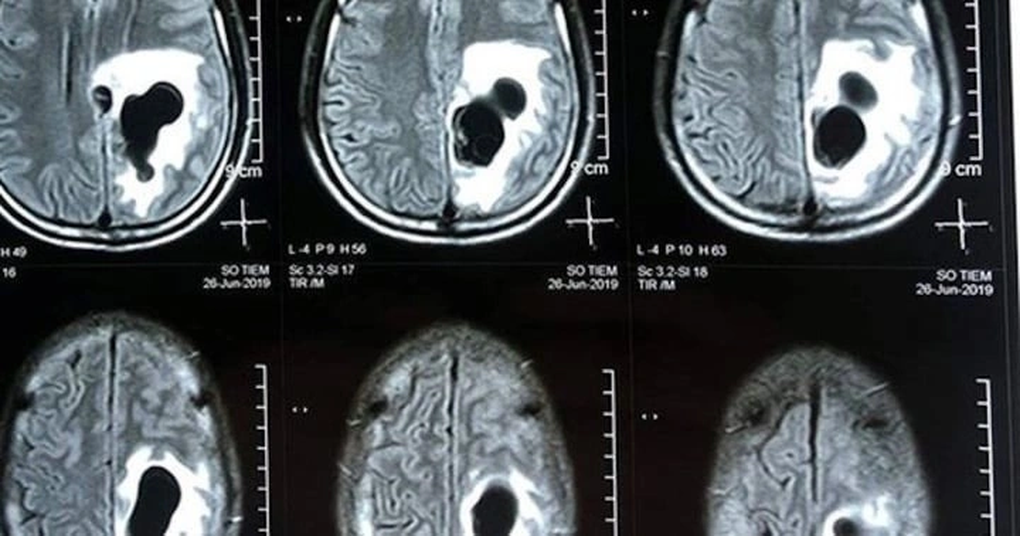

(Dân trí) - Chụp cộng hưởng từ sọ não thấy khối tổn thương ký sinh tại vùng não của bệnh nhân do ấu trùng sán dây lợn.

Theo TS.BS Trần Huy Thọ, Phó giám đốc Bệnh viện Đặng Văn Ngữ, kết quả xét nghiệm ELISA của bệnh nhân dương tính với ấu trùng sán dây lợn. Chụp cộng hưởng từ sọ não thấy khối tổn thương ký sinh tại vùng não của anh Trường do ấu trùng sán dây lợn.